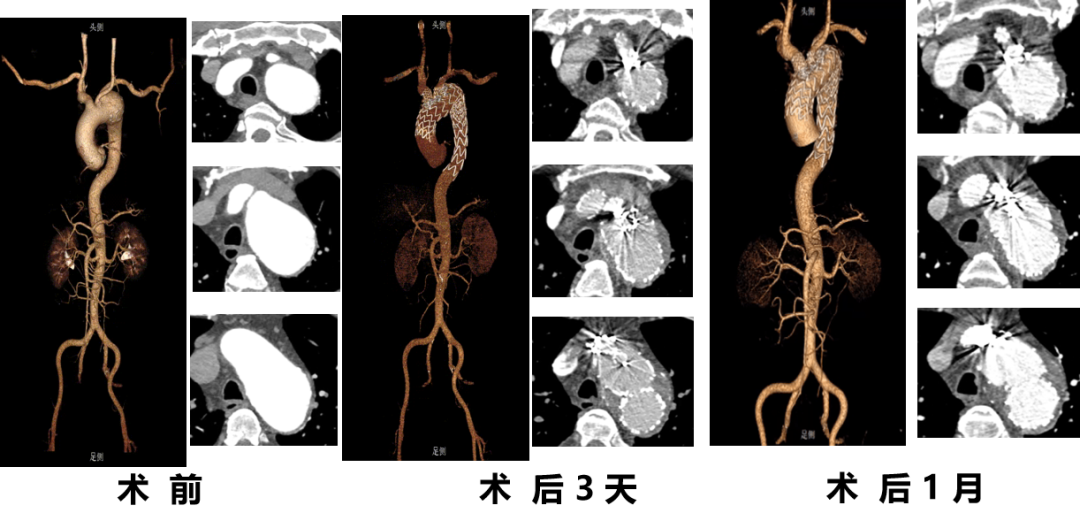

★ 病例2:模块内嵌分支胸主动脉覆膜支架系统

术前

术后